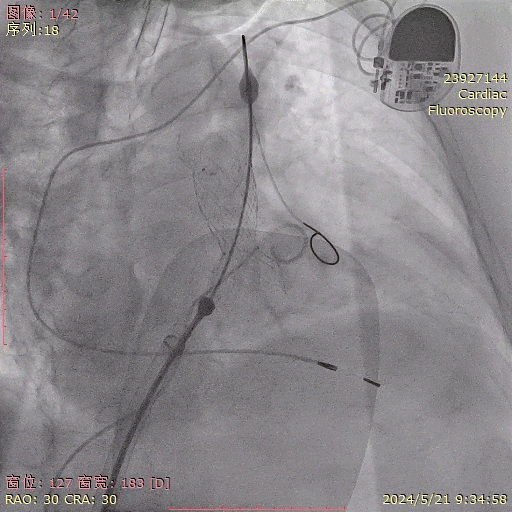

venusp-valve瓣膜释放完成,位置准确,瓣架形态稍受限将输送器送至肺